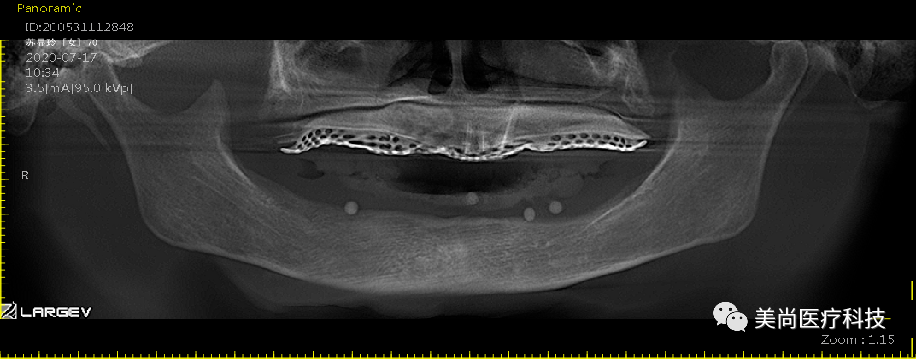

取模即刻负荷戴牙

永久修复

戴牙完成